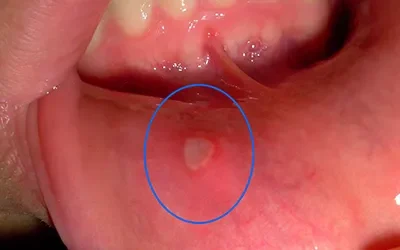

The Painful Truth: Understanding Oral Ulcers

Understanding Oral Ulcers Oral ulcers are a common condition that affects many people at some point in their lives. They can be uncomfortable and sometimes painful, but most ulcers are harmless and will go away on their own. In this blog, we will explore the causes of...